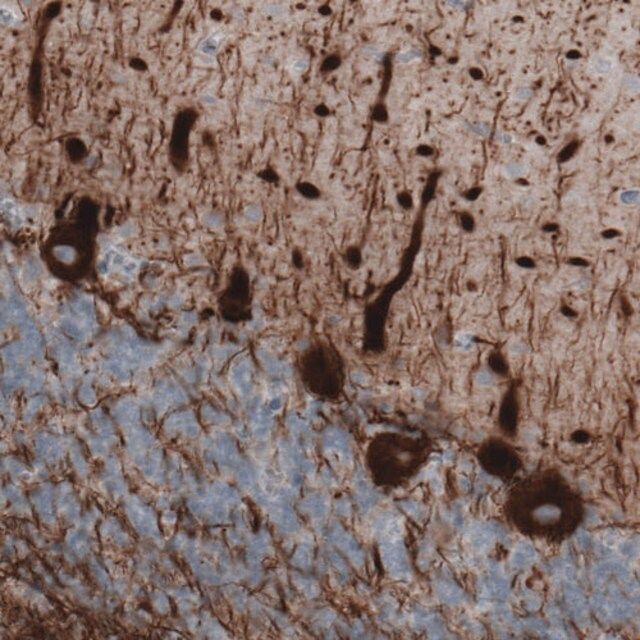

免疫原

neurofilament, medium polypeptide

| technique(s) | immunoblotting: 1 μg/mL immunohistochemistry: 1:5000- 1:10000 |